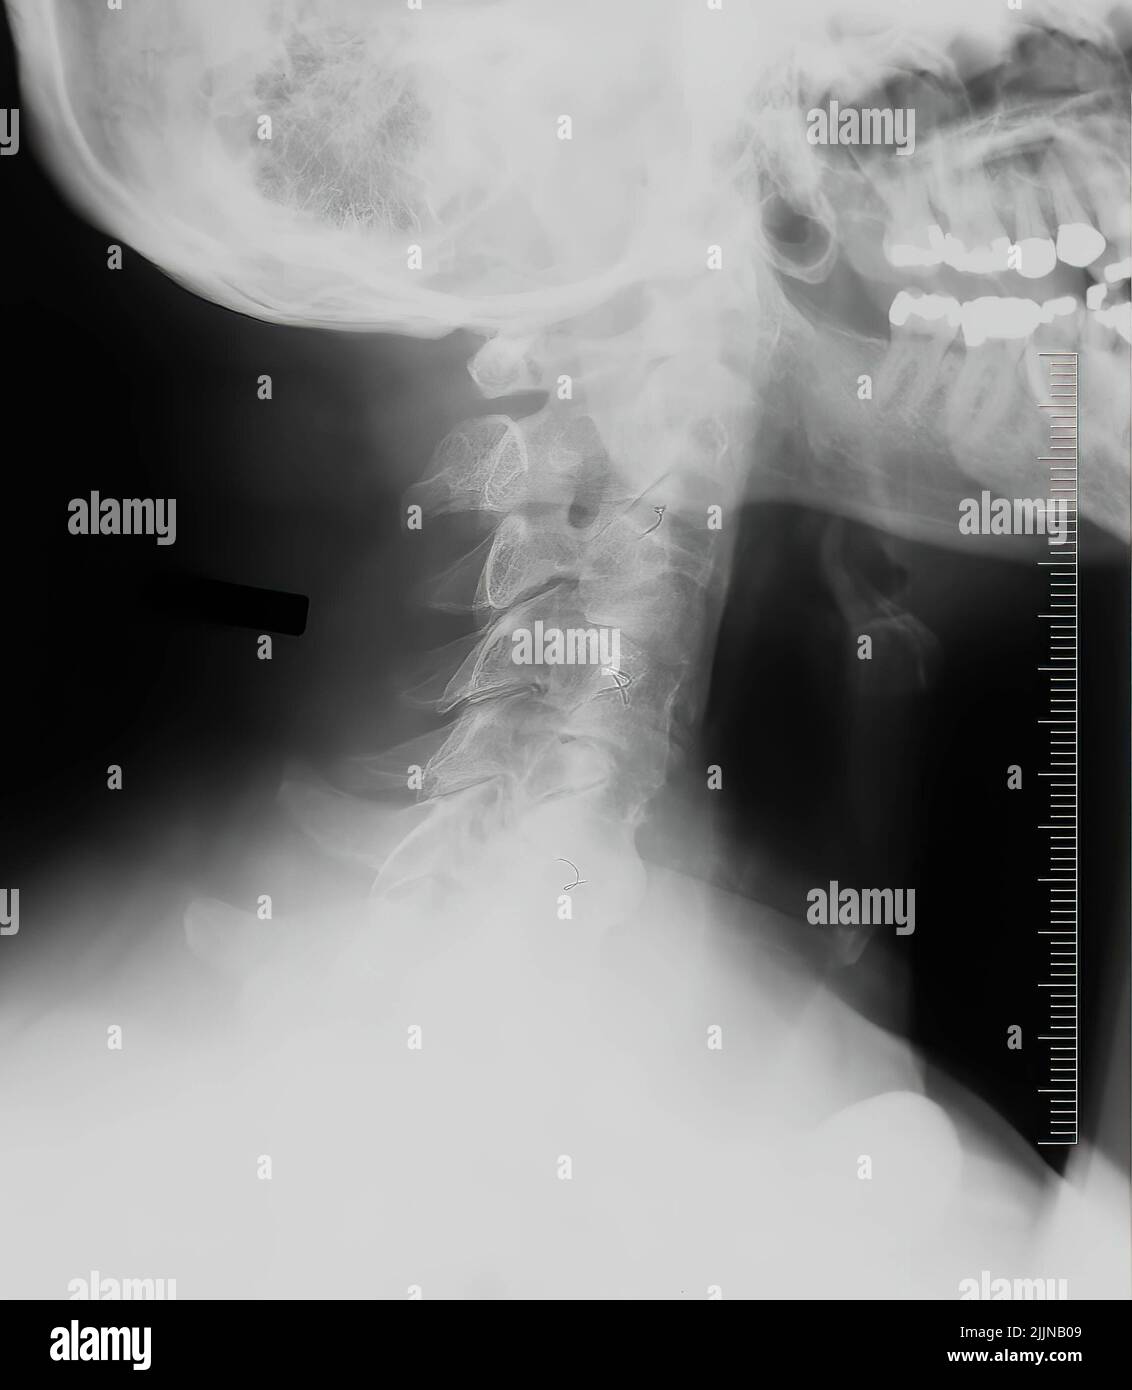

Source: bisonaidxwe.pages.dev Les vertèbres cervicales mâles verticales à rayons X. Concept médical Photo Stock Alamy , Le système vestibulaire est un organe sensoriel de l'oreille interne Ces disciplines permettent une mobilisation contrôlée de vos vertèbres cervicales et soulagent les tensions musculaires chroniques